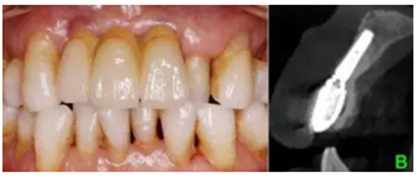

1.臨床病例:患者,男,年齡73歲,不慎摔倒至右上頜側(cè)切牙、左右上頜中切牙外傷根折,X線檢查:12、11、21折裂線達(dá)牙頸部以下。CBCT檢查:12、11、21折裂線呈水平狀,達(dá)牙頸部以下。

結(jié)合PRF的位點(diǎn)保存術(shù)后牙槽嵴輪廓豐滿,CBCT示骨量充足,數(shù)字化種植外科導(dǎo)板輔助下植體植入三維位置精確,種植體骨結(jié)合良好,數(shù)字化口掃系統(tǒng)數(shù)據(jù)采集高效、精確,臨時(shí)修復(fù)體戴入,軟組織成形,最終修復(fù)體戴入后穩(wěn)定、密合,牙齦軟組織色澤形態(tài)正常,美學(xué)效果良好。